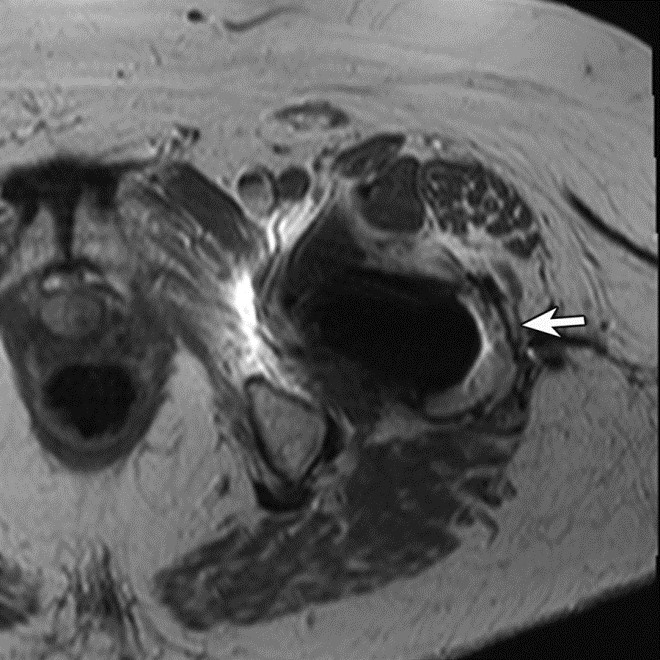

Adverse reaction to metal debris with posterior pseudotumor. Axial T1-weighted fast spin echo (FSE) (A) and STIR (B) MR images demonstrate left peritrochanteric fluid collection (arrow in A and arrowheads in B) arising from the left hip joint in a patient with metal-on-metal hip arthroplasty. Note the thin low T2 signal rim surrounding the fluid collection representing metal deposition. |

Adverse reaction to metal debris with anterior pseudotumor. Axial T1-weighted MR image shows large soft tissue mass (arrowheads) centered at the level of the lesser trochanter with involvement of the iliopsoas attachment site in a patient with metal-on-metal hip arthroplasty. Also note infiltrative involvement of the rectus femoris muscle.